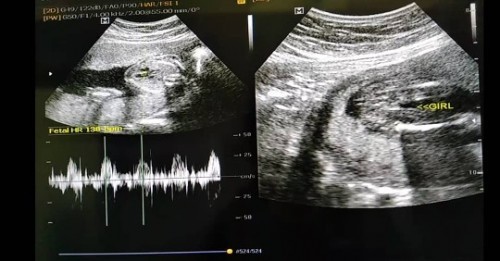

ช่วยดูเพศหน่อยค่ะ

ผู้หญิง หรือ ผู้ชายค่ะ

น่าจะผู้ชายนะคะ ตรงกลางหว่างขาเหมือนมีจู๋แหลมๆ บ้านนี้ก็ผู้ชายจ้า

จู๋โผล่ชัดเจนมากค่ะ ถ้าผู้หญิงจะเป็นร่องโพลงแบบนี้ค่ะ

น่าจะผช.นะคะ เห็นแหลมๆเหมือนปิกกาจูเลยค่ะ😂

น่าจะชายค่ะ เห็นมีเหมือนจู๋แหลมๆ